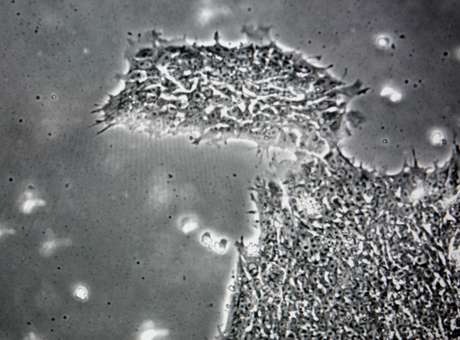

Um vírus que infecta o cérebro do ser humano e o torna mais “estúpido” foi descoberto por cientistas americanos. O chamado vírus “algae” não havia sido detectado anteriormente em pessoas saudáveis, mas foi encontrado em análises microscópicas de gargantas, podendo causar alterações nas funções cognitiva e visual.

Cientistas da Escola de Medicina Johns Hopkins e da Universidade de Nebraska fizeram a descoberta “sem querer”, durante um estudo de micróbios na garganta. Surpreendentemente, as pesquisas encontraram DNA que batia com o do vírus em pessoas saudáveis.

A pesquisa contou com 90 voluntários, sendo que 40 foram testados como positivo para a presença do algae. Aqueles que têm a presença do vírus se saíram pior em testes de avaliação de medidas, velocidade e processamento visual. Eles também obtiveram pontuações inferiores em tarefas concebidas para medir a atenção.